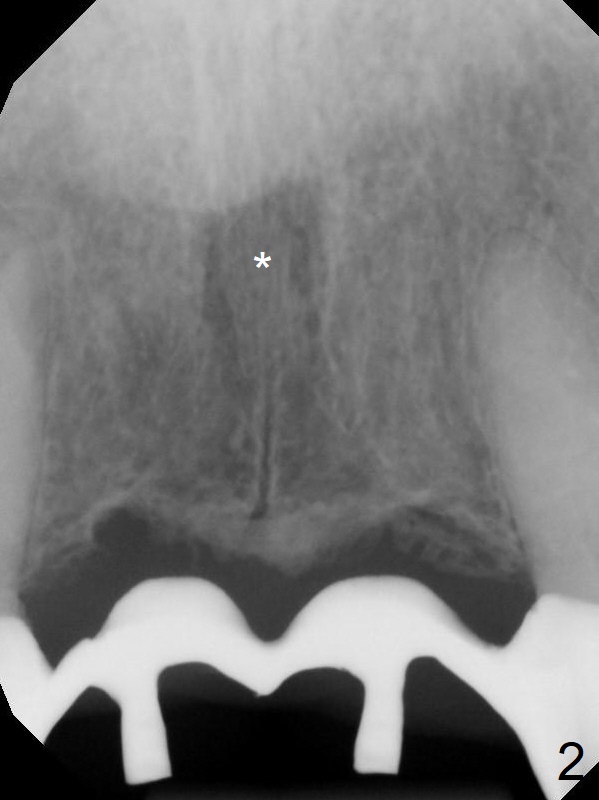

A 45-year-old Spanish woman requests implants to replace #7-10 FPD (Fig.1,2,7). After incision, osteotomy is initiated in the palatal aspect of the crest with 1.2 mm drill and DIO Bone Expanders (E1 (diameter 1.0/1.6 mm),E2 (1.3/2.3 mm), Fig.3,4). Following adjustment of the trajectory (to avoid invasion of the Incisive Canal (Fig.2 *) and use of E3 (1.7/3.1 mm), two of 3.5x11.5 mm HIOSSEN implants are placed with satisfactory stability (Fig.5). With Vanilla graft (Fig.5 *) placed over the palatally-exposed coronal threads, the flaps are approximated (Fig.6). The FPD is recemented temporarily (Fig.7).